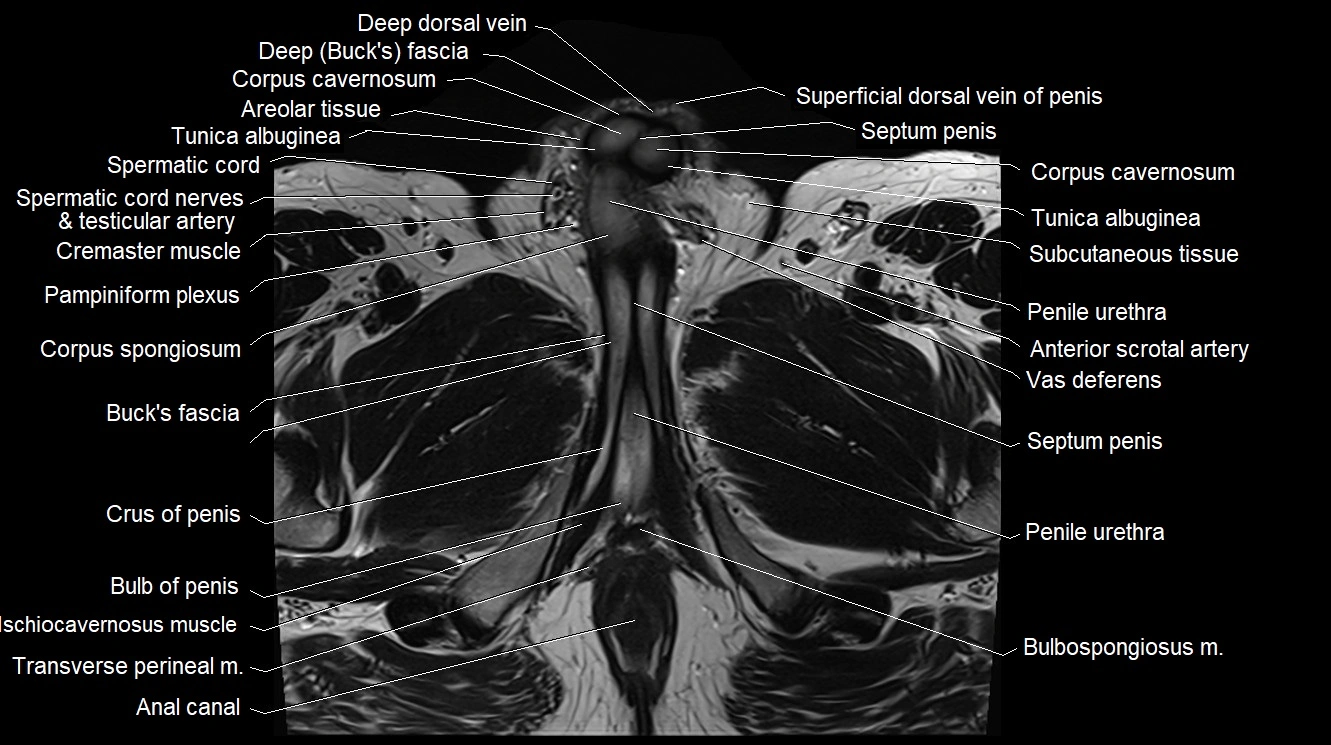

MRI image